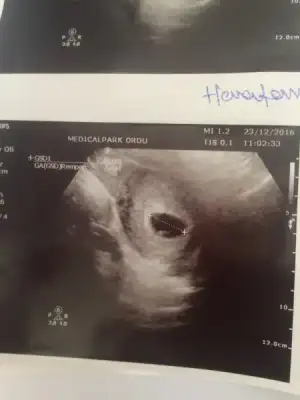

arkadaşlar bunuda yorunlarmısınız karından ultrason

Sizce erkek mi ? Karında saga yakın :) kesin dogru mu cıkıyor ya ..

Ay ınce uzun cıkmıs baya :) ben acemiyim ama kesede boyle uzun ince olunca erkek dıyorlar canım.allah saglıkla kucagına almayı nasip etsin